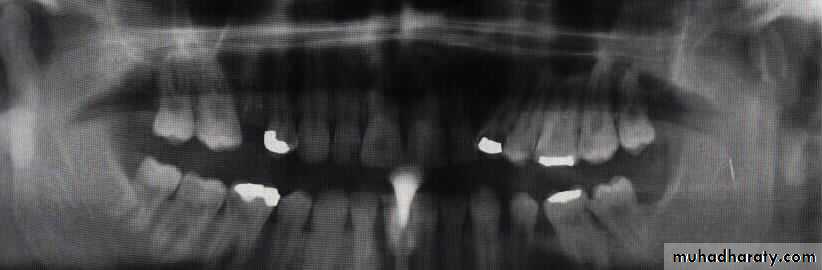

Radiographic evaluation:

Plain radiographOPG

Lateral oblique

PA mandible

AP mandible (reverse Townes)

Lower occlusal

CT scan

3-D CT imaging

MRI